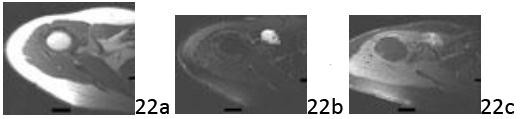

Question 22 A 24-year-old woman has had a mass on her right shoulder for the past 3 months. The mass is intermittently painful, warm, and swollen, particularly after periods of activity. Rest and ice relieve her symptoms. Radiographs are normal. T1-, T2-weighted, and contrast-enhanced MRI images are shown in Figures 22a through 22c. What is the most likely diagnosis?

Question 22 A 24-year-old woman has had a mass on her right shoulder for the past 3 months. The mass is intermittently painful, warm, and swollen, particularly after periods of activity. Rest and ice relieve her symptoms. Radiographs are normal. T1-, T2-weighted, and contrast-enhanced MRI images are shown in Figures 22a through 22c. What is the most likely diagnosis?

1. ## Synovial cell sarcoma

2. ## Carcinoma metastatic to soft tissue

3. ## Muscle tear with hematoma formation

4. ## Abscess

5. ## Intramuscular hemangioma

DISCUSSION: The lesion is an intramuscular hemangioma. Imaging characteristics can appear quite aggressive, and sarcoma is often in the differential. Fat is a prominent feature in diagnosing these tumors. In addition contrast aids in demonstrating the vascular channels, particularly in cavernous subtype. No necrosis or rim enhancement is demonstrated and no appreciable mass effect is noted, making malignancy or abscess less likely. A muscle tear with hematoma formation could have a similar appearance, but the time course should have allowed for partial or complete hematoma resolution. Observation is generally the treatment of choice, but if symptoms are not relieved by noninvasive means, surgery, sclerotherapy, and sometimes embolization may have a role. The Preferred Response # 22 is 5.

DISCUSSION: The lesion is an intramuscular hemangioma. Imaging characteristics can appear quite aggressive, and sarcoma is often in the differential. Fat is a prominent feature in diagnosing these tumors. In addition contrast aids in demonstrating the vascular channels, particularly in cavernous subtype. No necrosis or rim enhancement is demonstrated and no appreciable mass effect is noted, making malignancy or abscess less likely. A muscle tear with hematoma formation could have a similar appearance, but the time course should have allowed for partial or complete hematoma resolution. Observation is generally the treatment of choice, but if symptoms are not relieved by noninvasive means, surgery, sclerotherapy, and sometimes embolization may have a role. The Preferred Response # 22 is 5.